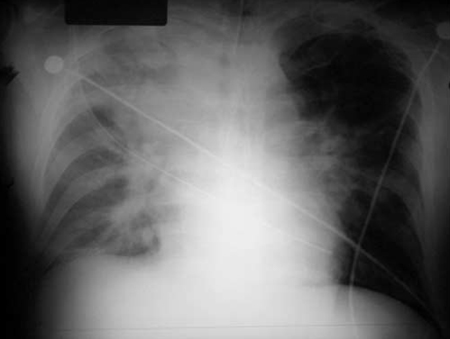

Anthrax

Chest x-ray findings of inhalation anthrax

Borio et al. JAMA. 2001;286:2554-2559